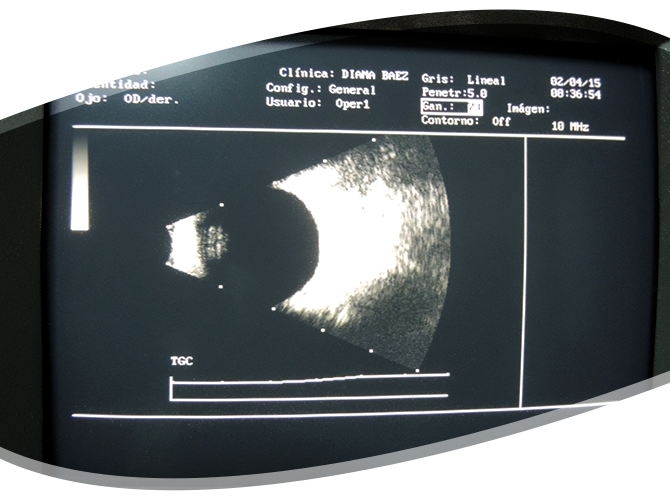

El modo B ó B Scan (B por brillante) produce cortes de imágenes tisulares bidimensionales, compuesta de puntos coalescentes de varios grados de brillantez, dependiendo de la reflectividad de la fuente de ecos.  Su aplicación en oftalmología es para determinar lesiones tumorales oculares, desprendimiento de retina, opacidades vítreas, anormalidades en el contorno ocular. Este método de diagnóstico es ideal particularmente en ojos con catarata avanzada y hemorragias masivas en vítreo los cuales no nos permiten distinguir directamente el interior del ojo. Este estudio se lleva a cabo con anestesia tópica (gotas oculares) y dura aproximadamente 15 minutos.